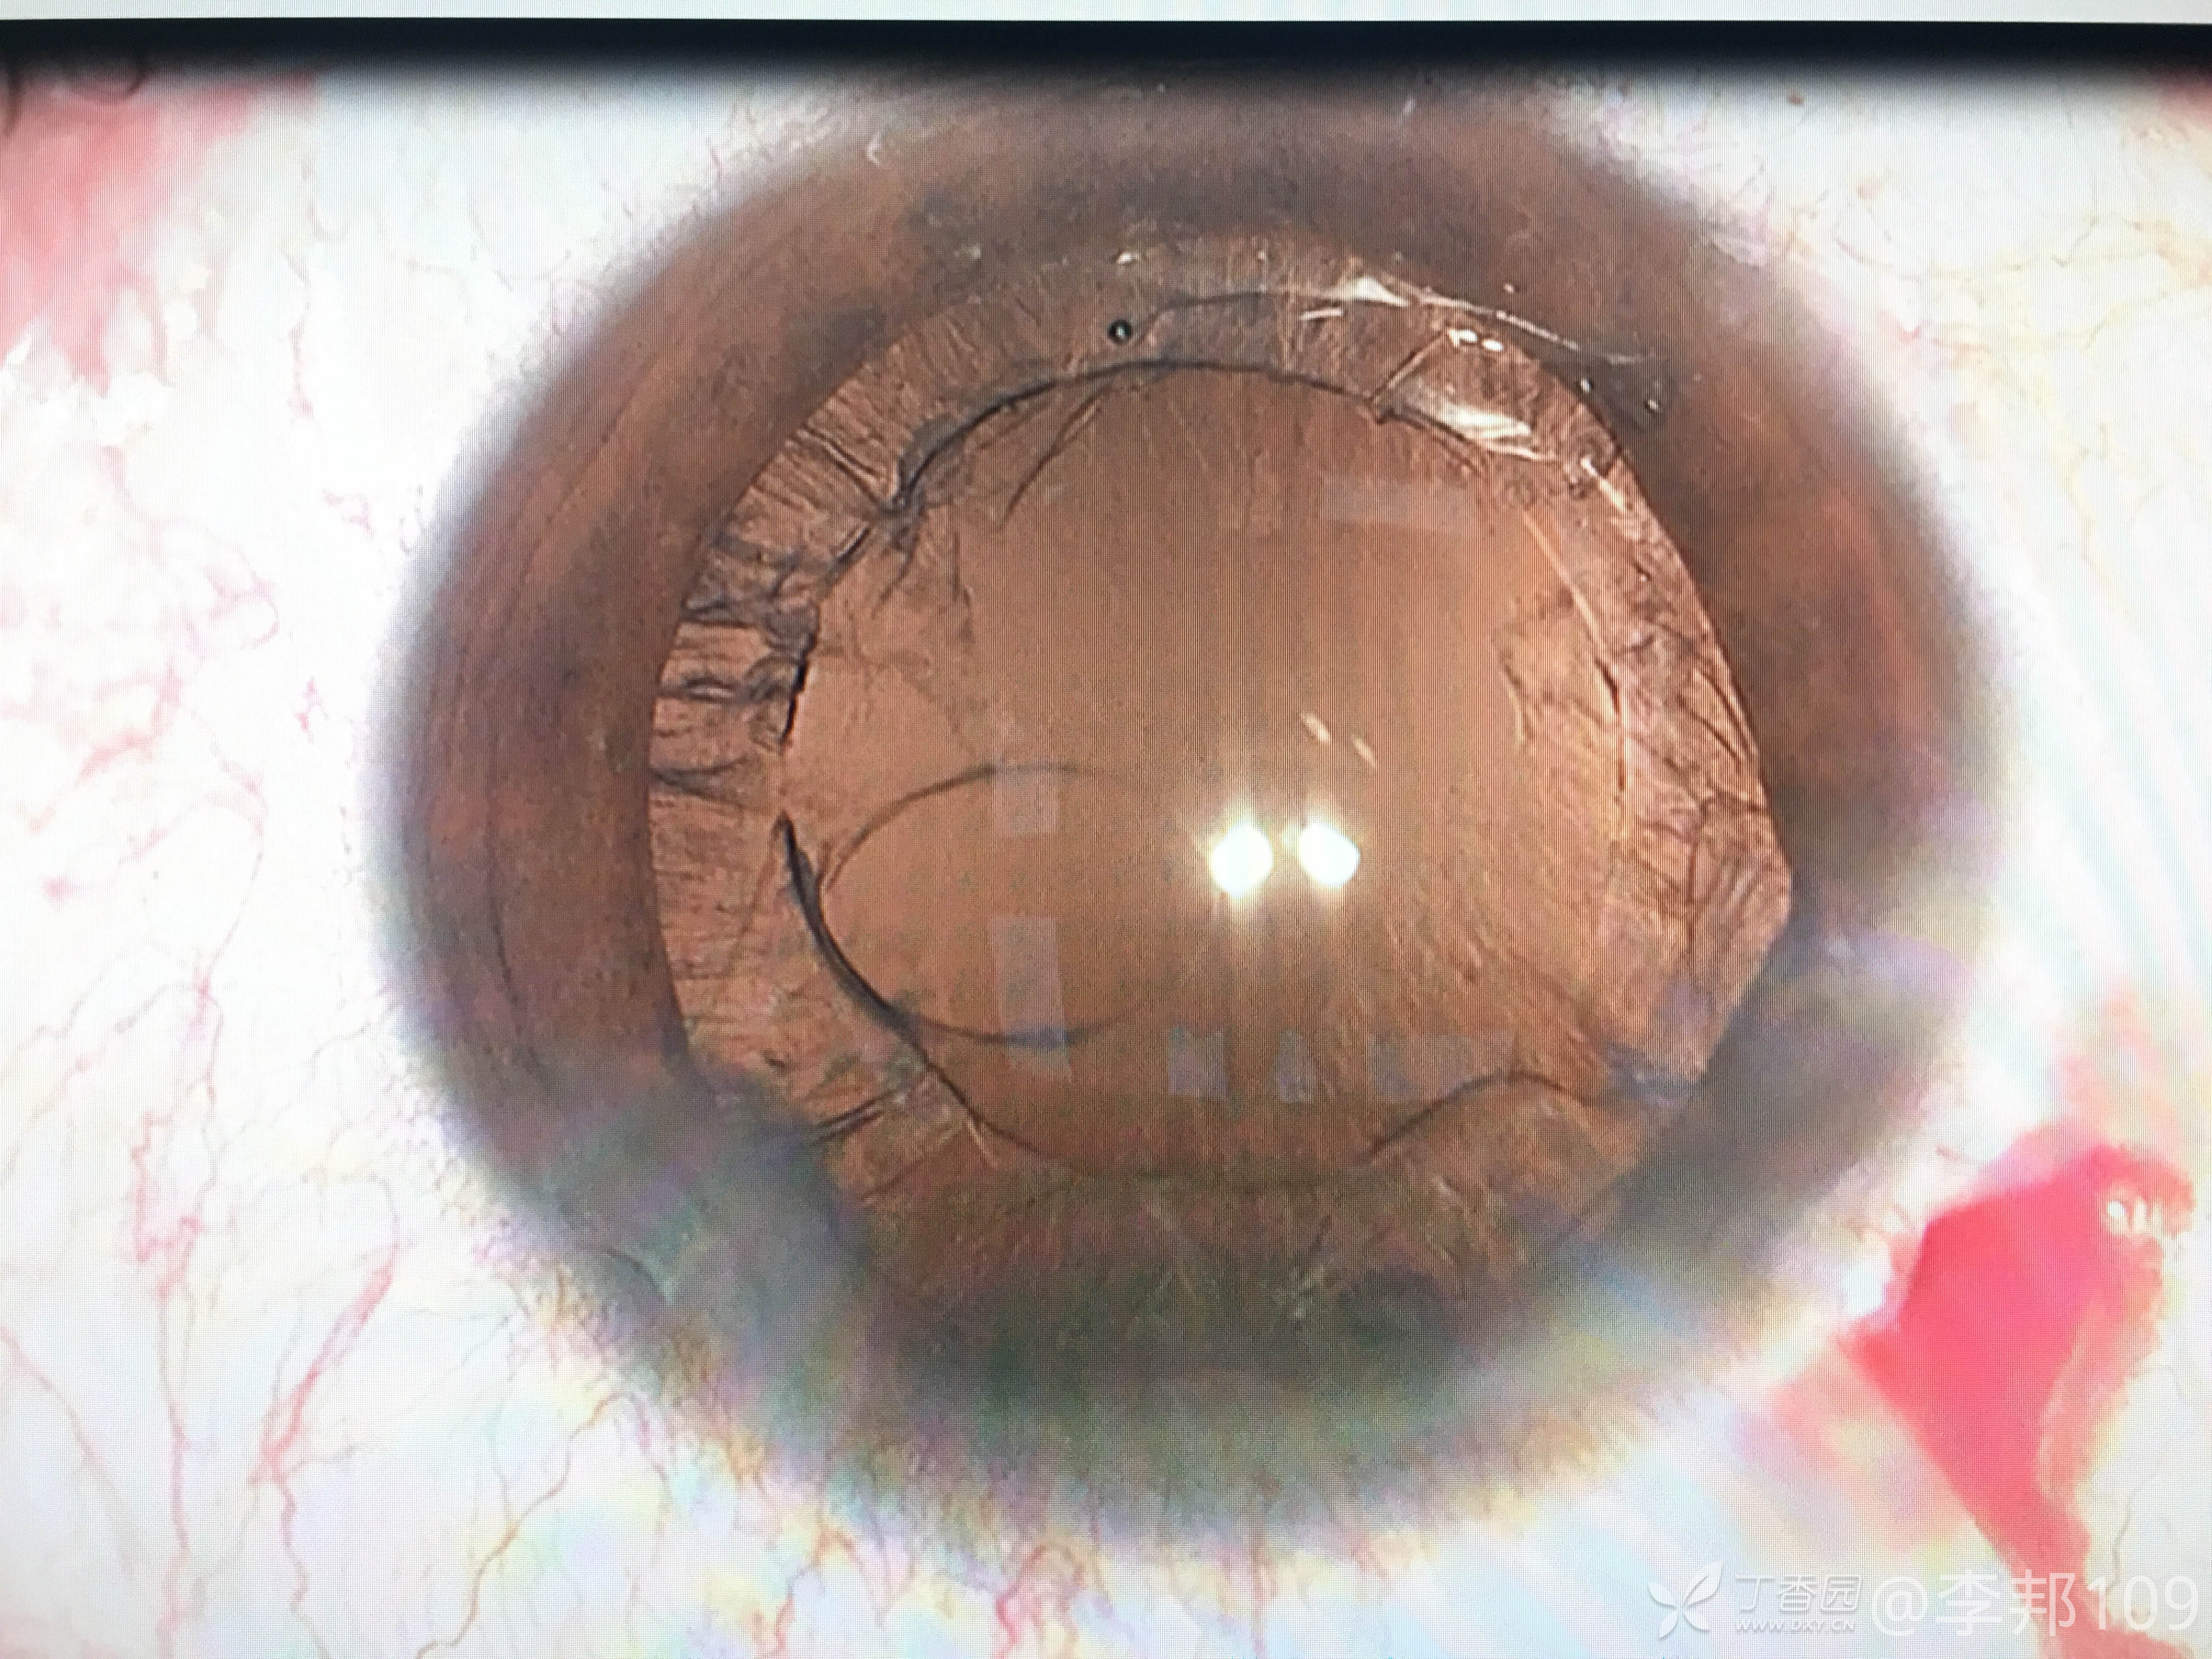

1.如何避免破后囊,破后囊之后,大家是怎么处理接下来的残留皮质?

2.这样的一个破口,人工晶体是放在睫状沟,还是囊袋内?

眼后囊膜破裂 (1)